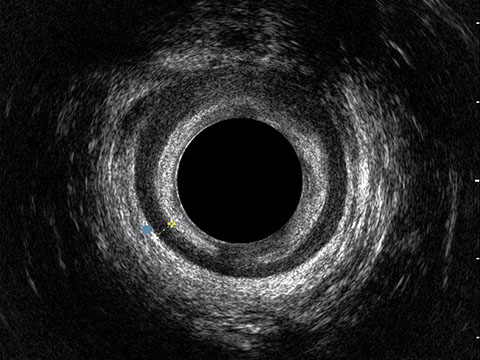

Proctal dispone di apparecchiatura per ecografia endoanale 3D con sonda rotante.

Sezione Longitudinale 3D con Tramite Fistoloso Intersfinterico Basso Anteriore Semplice